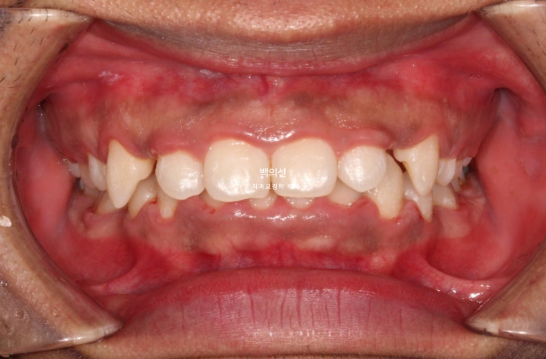

2년 전 교정치료를 이어받기 위해 오신 외국인 환자분입니다.

외국에서 발치교정 진행 중 브라켓을 붙인 채로 치료 도중 오셨으며 한국에 머무르게 되어 치료 마무리를 위해 오셨습니다.

사진은 브라켓을 뗀 후 사진이고, 위 앞니가 아랫니를 많이 덮는 과개교합이 보입니다.

아랫니가 안 보일 정도의 심한 과개교합 입니다.

위 아래 발치공간이 절반 이상 남아있는 상황입니다.

단순 발치공간을 닫는데 집중하기 보다는 앞니를 위로 올려 거미스마일도 해결하기로 합니다.

클리피씨 장치 부착하고 치료를 시작합니다.